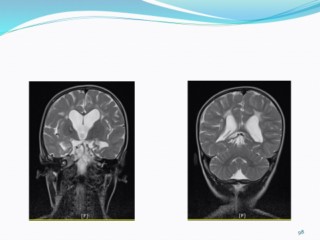

Tuberous Sclerosis Complex